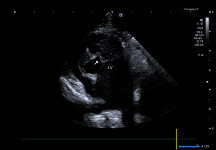

- 좌심방 및 좌심방이 내부에서 Spontaneous Echo Contrast(SEC) 가 관찰되었는데, 이는 혈액 흐름이 느려지면서 혈전이 생기기 쉬운 상태임을 의미합니다.

환자의 심장초음파 사진(좌심이 내 spontaneous echo contrast (SEC) +) / 출처: 24시 동탄리더스동물의료원